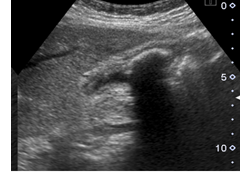

癌王-胰臟癌

2022.06.01

內視鏡超音波 - 早期診斷胰臟癌的利器